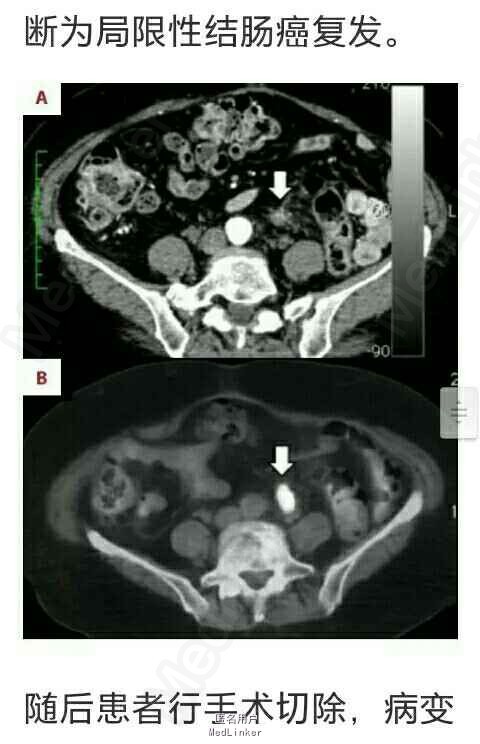

1年半后患者CT检查提示腹主动脉分叉处左侧见一边界模糊,非肿瘤性病灶,血供丰富。考虑为术后结缔组织的炎症反应。随后几次复查发现该病灶形态逐渐改变。术后3年CT检查结果显示病灶体积增大,但放射学检查依旧认为是良心病变。术后5年复查,上述病灶在CT上呈实性肿瘤样改变,其内可见骨针形成,怀疑为结肠癌术后局限性复发。但CEA和CA199等肿瘤标记物未见异常。为证实肿瘤存在,患者行FDG-PET/CT检查。检查结果示:上述病灶呈明显FDG高摄取,除上述病灶外未发现其他存在病灶,诊断为局限性结肠癌复发。

随后患者行手术切除,病变位于左侧输尿管与腹主动脉及分支之间。术后标本肉眼观可见肿块由结缔组织组成,包括白色和坚韧的瘢痕组织。组织学病例结果显示为良性脂肪组织,包括纤维血管成分。